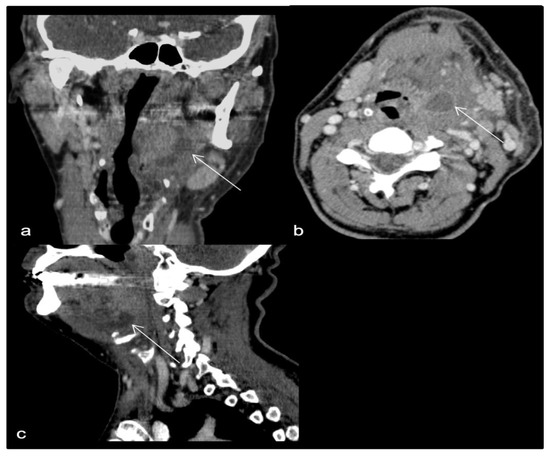

- Case 1.

- Case 2.

- Case 3.

- Case 4.